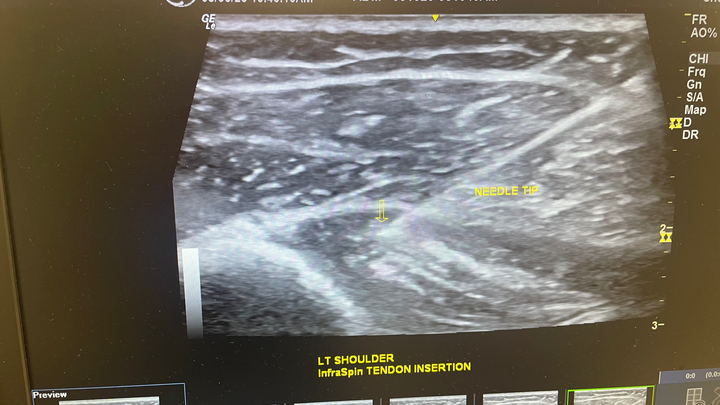

On the 4th of July she was lifted off the ground by her rib cage and tilted and continuously squeezed. Her two ribs 5&6 were popped out and now she is in constant agonizing pain!

These treatments consist of chiropractic rib adjustments and Prolo Therapy injections that only an MD can perform. The treatment will last anywhere from 16-24 weeks weeks!